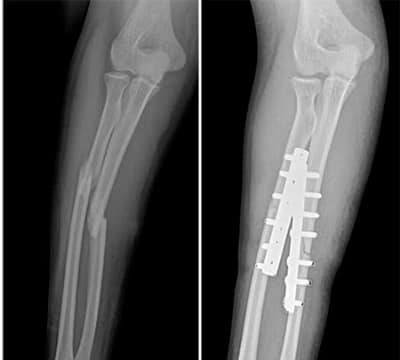

Chơi vật tay, nam thanh niên tập gym bị gãy tay